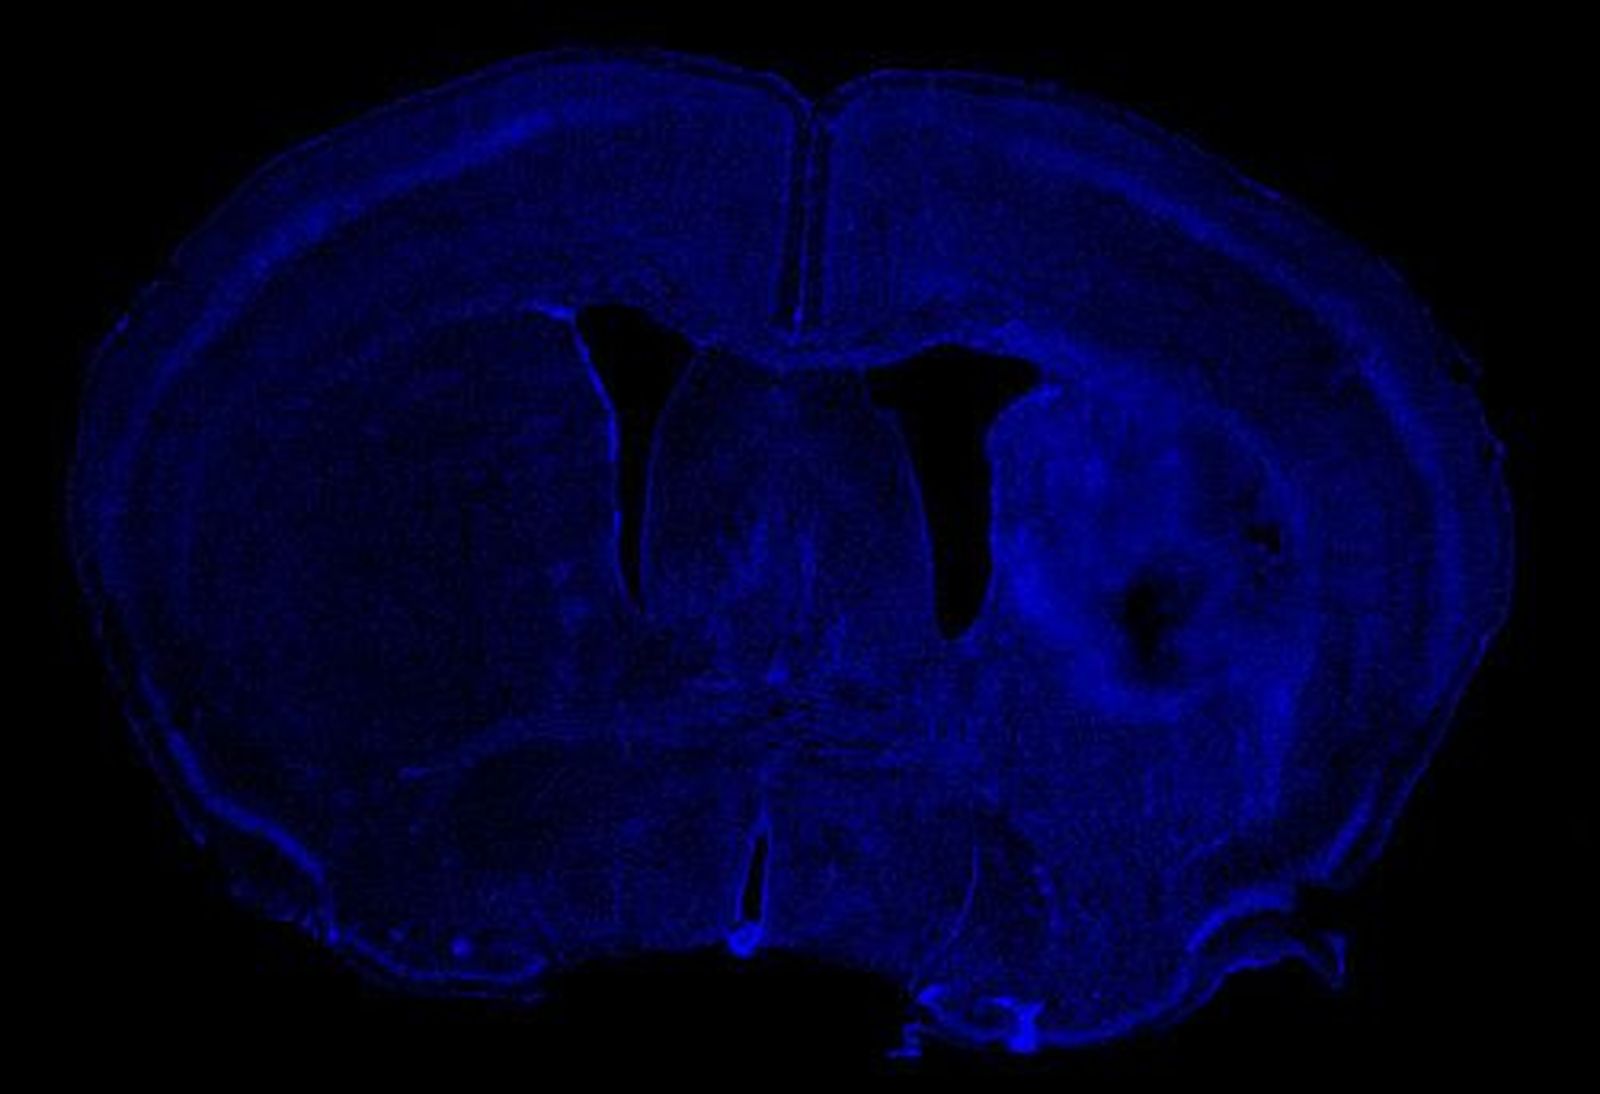

Hemorragia cerebral con lesión en el hemisferio derecho. Imagen: Neurobiología Molecular

Dentro de la hemorragia cerebral, algunos pacientes evolucionan mejor que otros aunque tengan el mismo daño y el motivo tiene que ver con su genética. “Hemos encontrado un marcador genético, una mutación puntual que se produce en parte de la población y que está relacionada con un mayor daño cerebral y una peor recuperación. Esto significa que los pacientes que la tienen requieren mayor rehabilitación para poder recuperarse”, afirma.